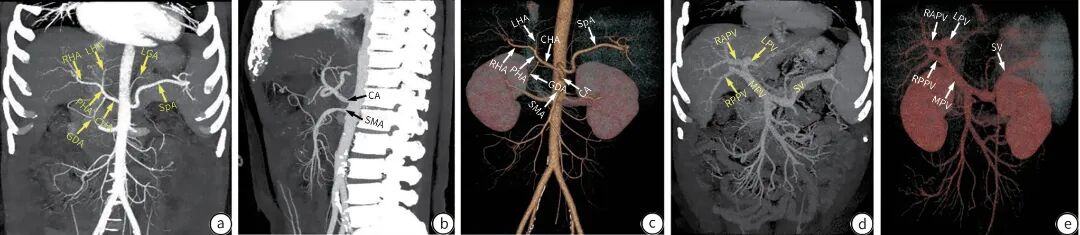

计算机体层血管造影(CTA)是目前临床常用的一种肝脏血管成像检查技术,可清晰观察血管分支结构,后处理技术可任意方位、层面观察肝脏血管,清晰显示解剖结构、狭窄程度、栓子和血管细小分支(图2)。肝脏CT灌注扫描是一种无创性评价组织器官血流灌注状态的功能成像方法,通过时间-密度曲线可评价组织器官的血流灌注状态。

注: a、b, CTA最大密度投影(MIP)显示肝动脉系统;c, CTA容积再现技术(VR)显示肝动脉系统;d、e, MIP、VR技术显示门静脉系统。CTA,计算机体层血管造影;CA,腹腔干;CHA,肝总动脉;SpA,脾动脉;PHA,肝固有动脉;GDA,胃十二指肠动脉;SMA,肠系膜上动脉;RHA,肝右动脉;LHA,肝左动脉;LGA,胃左动脉。

图2 肝血管CTA示意图